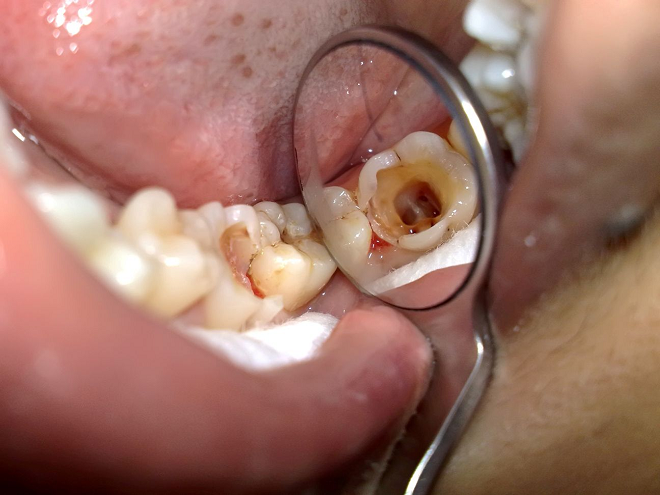

- Kháng Sinh – Chống Viêm

- Thuốc tiêu hóa, dạ dày